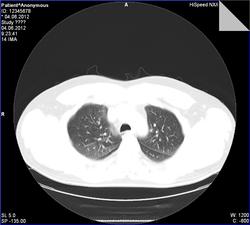

- https://radiomed.ru/sites/default/files/styles/case_slider_image/public/user/7898/009.jpg?itok=5McfrAtx

сделать снимок на выдохе для исключения обструкции

Обогащение рисунка, снижение пневматизации. сказать что -то конкретное -трудно. Сосудистое окно бы посмотреть. На выдохе- да было бы неплохо.

Расширение? верхнего этажа переднего средостения. Мягкотканное окно?

Ничего такого, что обуславливает одышку тут не видно. Хорощо бы полистать дайком. Ну еще надо бы посмотреть кровушку и тесты ФВД.

В общем-то, бросилось в глаза то, что расширены вены, преимущественно, нижних долей. При этом правые и левые венозные коллекторы без явного расширения и аномалий, предсердие с ушком без проблем при нативной КТ. Так же заметил "нежные" ретикулярные изменения в переднем сегменте верхней доли справа.

Ой, прошу прощения! Я тормоз! Там же 3 серии: 1 - топограмма, вторая на вдохе, а третья - на выдохе)))) Сергей Николаевич, Ваши иллюстрации с серии на выдохе.Радостно посмотрела на вдохе - чисто!

Пример скана на одном уровне при фазах дыхания).

По экспираторной КТ - норма, "ловушек" нет, значит и обструкции нет, что и требовалось доказать, что соответствует заключению по ФВД ( сам интерпретировать параметры не смогу полноценно, со времен учебы подзабыл, а во время работы вникать в цифры не приходилось). Может, кто разбирается и прокомментирует.

Предоставленные в первом посте томограммы - экспираторная КТ, можно не только на слово

Томография: рентгенологически патологии не визуализировано